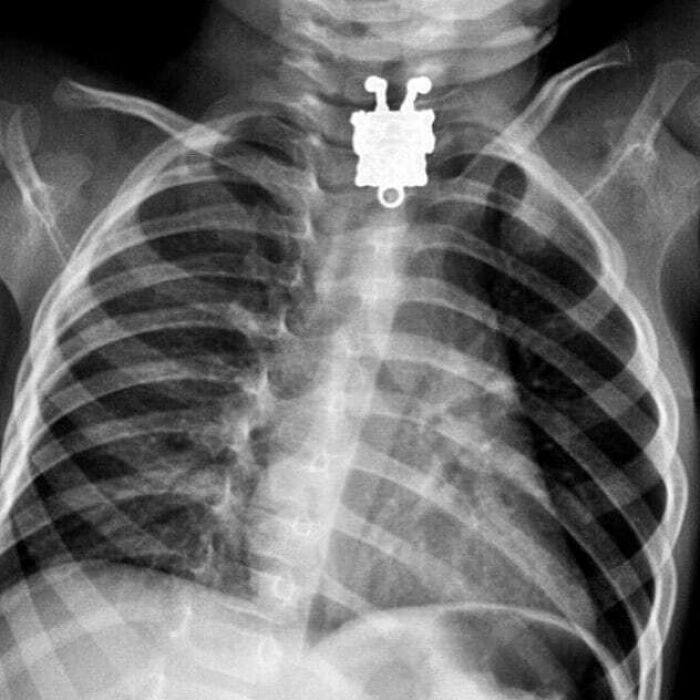

#63 X-Rays Of A 16-Month-Old Boy Who Swallowed A Spongebob Squarepants Necklace Pendant

Doctors who scanned a toddler's chest to try and discover what he had swallowed were shocked to find an image of the cartoon character SpongeBob SquarePants staring back at them. Doctor said the detail on the pendant was so clear because it was made up of tiny ridges in the metal's surface. The pendant was removed from the boy's throat and he was discharged to recover at home.